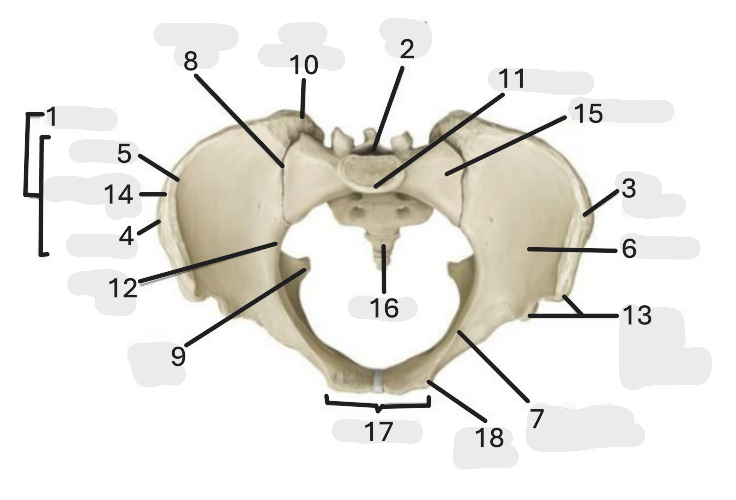

Where is the pelvic inlet

1

Where is the sacro-iliac joint

2

Where is the pubic tubercle

3

Where are the S1 body

4

Where is the ischial spine

5

Where is the ala of sacrum

6

Where is the anterior superior iliac spine

7

Where is the ischiopubic ramus

8

Where is the coccyx

9

Where is the obturator foramen

10

Where is the pubic symphysis

11

Where is the ischial tuberosity

12